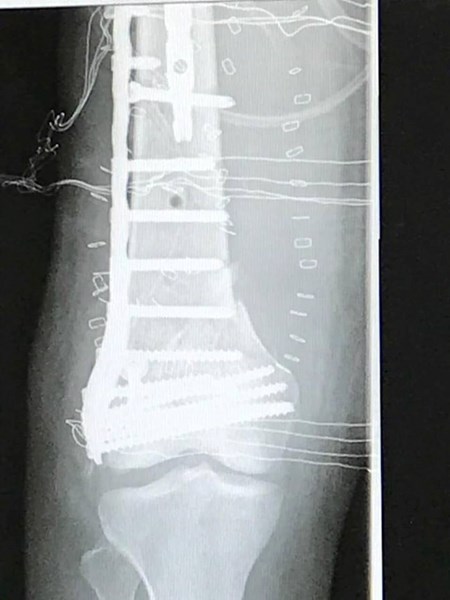

Моделът Кристин Илиева отново е в истанбулската болница "Йедитепе", където бе приета по спешност преди няколко дни, научихме от "168 часа". 20-годишната красавица трябваше отново да постъпи там само седмица след завръщането си у дома след 33-дневен престой в лечебното заведение в турския мегаполис.

Вследствие на костна инфекция Кристин вдига висока температура и родителите й са посъветвани от специалистите, които следят нейното състояние, да бъде върната обратно в "Йедитепе". "168 часа" научи още, че в истанбулската болница моделът е подложена на операция за овладяване на инфекцията.

Още преди възникването на този проблем Кристин започва своята тежка възстановителна програма. Тя трябва да премине през задължителна рехабилитация и всеки ден да работи с физиотерапевт. Този етап от лечението й също е много труден и болезнен за нея. От красавицата се изисква да прояви силен характер, за да развижи по-скоро десния си крак, който в момента е с частична парализа. В същото време специалистът, който работи с нея, не желае да я пресира, защото все още има риск за крака й.